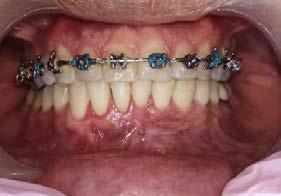

Su fonación no es clara, ya que presenta congestión nasal y hábito de lengua. Las fotografías intraorales de inicio se muestran en la Figura 2

Inicio de tratamiento, marzo del 2022 con aparato ortopédico funcional SN6 dando indicaciones de utilizarlo 24 horas y solamente retirarlo para

Clase II subdivisión I con mordida abierta por hábito de succión digital tratada ortopédicamente

alimentarse, activación una vez por semana durante 8 meses (Figura 3).

Sus citas fueron mensuales hasta la obtención de resultados favorables 8 meses después. Consiguiendo cerrar la mordida y obteniendo una línea dental favorable, terminando tratamiento con su aparato removible SN6 en noviembre del 2022 (Figura 4). Se dio de alta temporal, retirando su aparatología funcional.